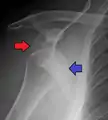

A Hill–Sachs lesion is an impaction of the head of the humerus left by the glenoid rim during dislocation.[6] Hill-Sachs deformities occur in 35–40% of anterior dislocations. They can be seen on a front-facing X-ray when the arm is in internal rotation.[9] Bankart lesions are disruptions of the glenoid labrum with or without an avulsion of bone fragment.

An anterior dislocation of the shoulder

Anterior dislocation of the right shoulder. AP X ray

Anterior dislocation of the right shoulder. Y view X ray.